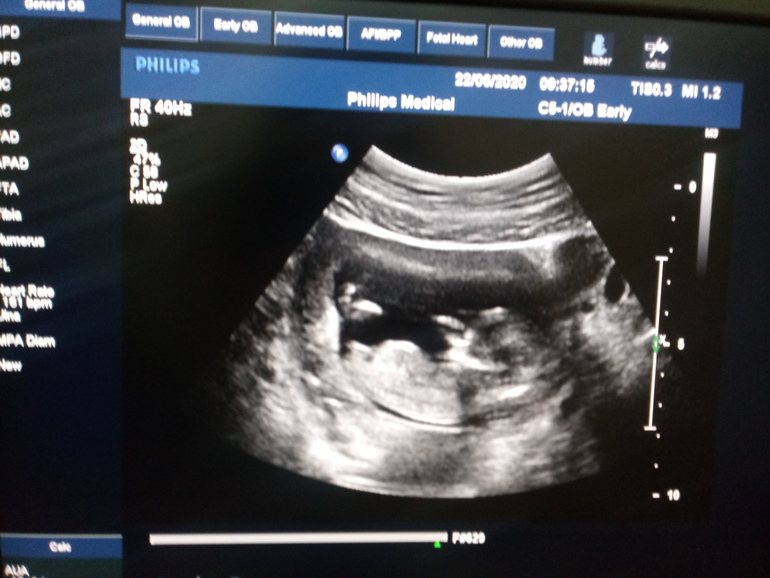

1 скринг пройден, свидание с малышочком состоялось)

Ну вот и я добралась до 1 скринга. С малышочком слава Богу все хорошо по узи, развиваемся как надо, ручки, ножки..все на месте. Сердечко тарахтит как моторчик. Надеюсь и с генетикой все будет хорошо.

Про пол молчат, говорят не видно еще ничего.

Вот такие вот мы крошечки...

Всегда удивляюсь людям, которые что-то понимают в этих снимочках. Я вот лишь очертания малышочка вижу.